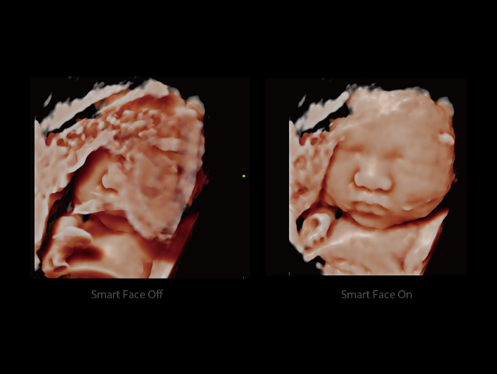

W aparacie DC-80A X-Insight zintegrowano inteligentne rozwi?zania z profesjonalnymi narz?dziami diagnostycznymi w ró?nych aplikacjach i podczas ca?ego cyklu badań: od pocz?tku ci??y, poprzez badania prenatalne, a? po opiek? poporodow?.

Obrazy kliniczne